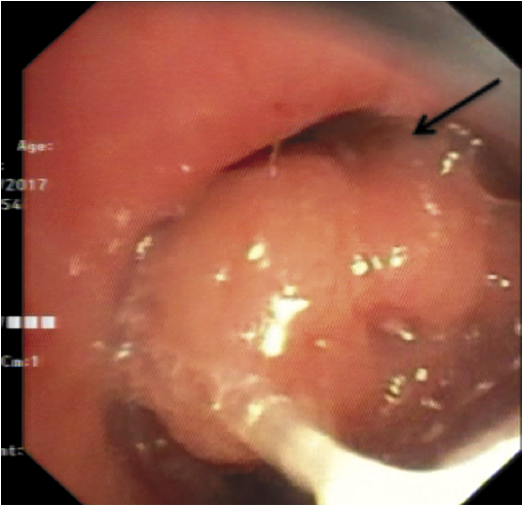

Для оценки опухоли носоглотки проведена фиброскопия верхних дыхательных путей. Эндоскоп проведен через левый нижний носовой ход, который у своего дистального края несколько сужен. Всю полость свода носоглотки занимает опухоль, исходящая из глоточной миндалины. Слизистая оболочка на поверхности опухоли имеет неоднородную окраску с участками гиперемии. Выполнена биопсия опухоли. Провести эндоскоп дистальнее и осмотреть область ротоглотки не представляется возможным. Результат представлен на рис. 2.

Рис. 2. Стрелкой указана опухоль, которая занимает носоглотку и пролабирует в хоану.

Fig. 2. The arrow indicates the tumor that occupies the nasopharynx and prolapses into the choana.